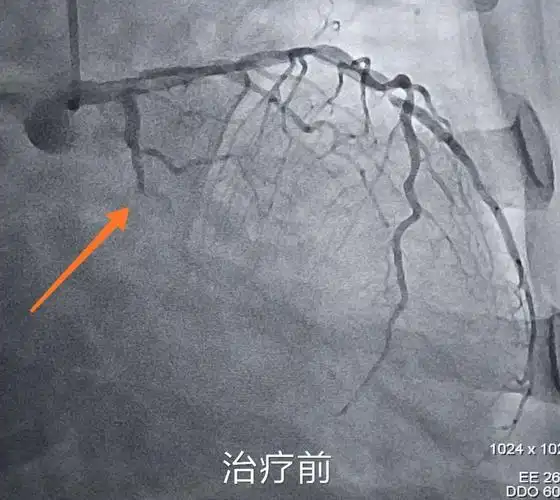

急诊冠脉造影示:回旋支近段闭塞.

冠脉造影提示右冠起始段多发狭窄,严重处狭窄约90%,并多发斑块形成.